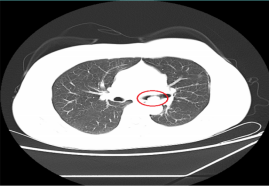

“小”内镜切除支气管“大”肿瘤 近日,一位患支气管肿瘤患者到我院呼吸内科治疗,检查时,其肿瘤几乎已经完全堵塞气管管腔,若不及时手术,随时可能发生呼吸衰竭。 情况危急,医生立即为其抽取动脉血化验并给予高流量吸氧等,但患者呼吸困难的症状缓解不明显,必须及时将肿瘤切除。“如果按照传统的手术方式,需将患者气管切开,组织损伤性高、流血量多。由于患者肿瘤贴近降主动脉,切除过程中将伴有大出血的风险。”刘碧翠说,随着我院内镜技术的发展,对于这样的重症患者,可以利用呼吸内镜迅速切除肿瘤,清理气道内局部的坏死组织、分泌物并予以止血处理。 科室介入团队经过精心准备后,立刻为患者实施内镜介入手术,将气道内肿物切除干净。手术仅用时2小时,患者没有发生大出血,很快便恢复出院。此次手术的成功开展,充分体现了呼吸内科对此类疑难危重气道疾病患者的救治能力。